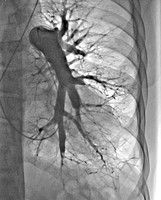

Uniwersyteckie Centrum Kliniczne, szpital Gdańskiego Uniwersytetu Medycznego dołączyło do wąskiego grona ośrodków kardiologicznych w Polsce wykonujących balonoplastyki tętnic płucnych (BPA) u pacjentów z zakrzepowo-zatorowym nadciśnieniem płucnym. Tym samym zainicjowano program inwazyjnego leczenia tej rzadkiej choroby w Klinicznym Centrum Kardiologii UCK kierowanym przez prof. Grzegorza Raczaka. Pierwszy zabieg wykonał zespół w składzie: dr Dariusz Ciećwierz i dr Grzegorz Żuk pod nadzorem prof. Marcina Kurzyny z Europejskiego Centrum Zdrowia w Otwocku, który jest pionierem tych zabiegów w naszym kraju.

Zakrzepowo-zatorowe nadciśnienie płucne to stosunkowo rzadkie powikłanie ostrej zatorowości płucnej. Zgodnie z aktualnymi wytycznymi Europejskiego Towarzystwa Kardiologicznego podstawową metodą leczenia inwazyjnego tych chorych jest operacja kardiochirurgiczna. Jednak leczenie przezskórne w postaci BPA zyskuje coraz bardziej na znaczeniu. Obecnie wykonuje się je u pacjentów, którzy zostali zdyskwalifikowani z leczenia kardiochirurgicznego lub u chorych po leczeniu operacyjnym, u których nie uzyskano optymalnego efektu leczenia.

Leczenie inwazyjne w postaci BPA to leczenie wieloetapowe rozłożone u każdego pacjenta na kilka sesji zależnie od lokalizacji zmian w krążeniu płucnym i wyników cewnikowania serca. Efekty, które udaje się uzyskać na podstawie doświadczeń innych ośrodków pozwalają na istotną poprawę wydolności fizycznej pacjentów i normalizację parametrów hemodynamicznych.